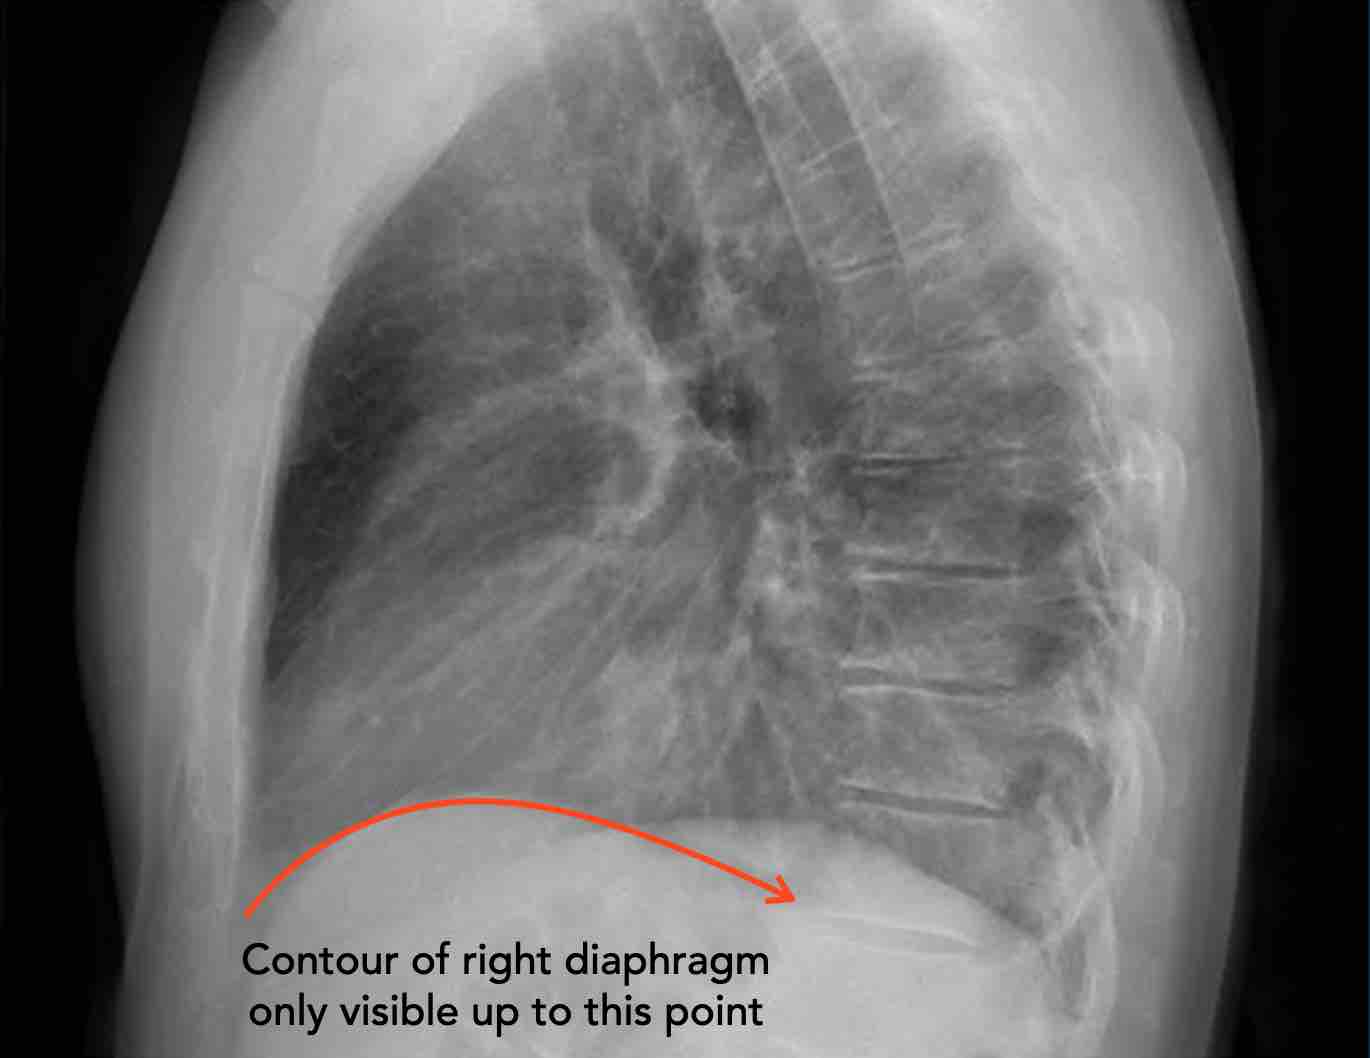

- Vòm hoành phải phải được nhìn thấy rõ ràng ở phía trước đến tận thành ngực (mũi tên đỏ), thể hiện ranh giới giữa phổi có khí và mô mềm ổ bụng.

- Vòm hoành trái thường chỉ nhìn thấy đến điểm tiếp giáp với bóng tim (mũi tên xanh lam), phía ngoài điểm đó ranh giới bị mất do tỷ trọng tương đương giữa tim và các tạng bụng phía trên.